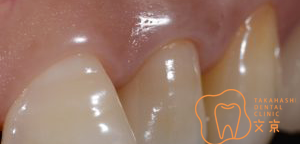

■歯肉圧排・精密審美治療について